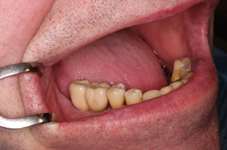

V případě chybění většího počtu zubů v postranních úsecích čelistí je možné ošetření pomocí implantátů, které nahradí ošetření pomocí snímacích náhrad kotvených na zbývajících zubech nebo patře.

Podmínkou je opět dostatečné množství kosti.

Protetické řešení může být pomocí můstku, který je kotvený na implantátech nebo pomocí jednotlivých korunek na implantátech.